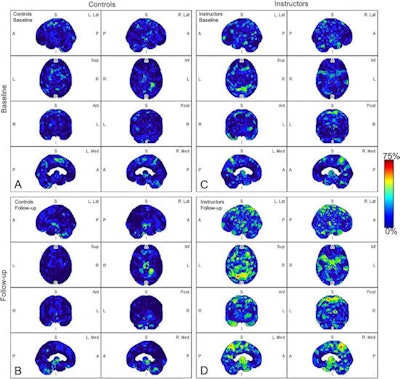

All instructors underwent baseline F-18 florbetapir PET scans and again five months after being exposed to repeated blast events during their training duties. Age-matched healthy control participants not exposed to blasts and without a history of brain injury were also evaluated at similar time points.

In a comparison between the groups, blast-exposed participants showed significantly increased amyloid deposition in four brain regions known to be abnormal in Alzheimer's disease: the inferomedial frontal lobe, precuneus, anterior cingulum, and superior parietal lobule. Conversely, no amyloid deposits were observed in the control participants.

"We found that most military instructors exposed to blast episodes had abnormal beta-amyloid brain deposition in the early phase after the subconcussive events," the researchers wrote.